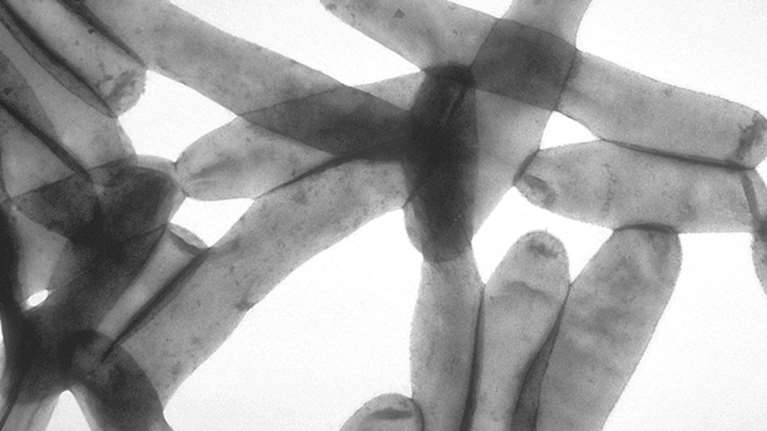

Η λεγεωνέλλωση είναι οξεία βακτηριακή λοίμωξη του αναπνευστικού συστήματος που προκαλείται από τα βακτηρίδια του γένους Legionellae.